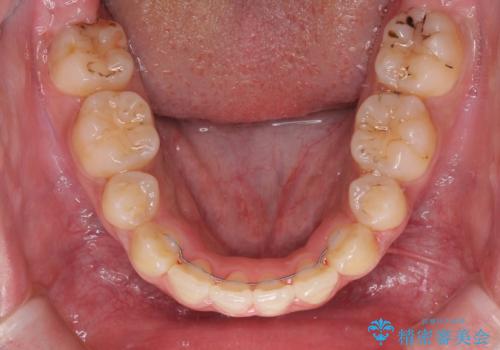

- メタルブラケット

- 2年1ヶ月

上下前歯部叢生のスペース獲得のため、上下顎左右小臼歯各1歯(計4本)と全ての親知らずを抜歯して、矯正治療を行うこととしました。

上下の正中位置が大きくずれていたため、治療期間の長期化や正中が合わないまま終了することが予想されましたが、思っていた以上にスムーズに歯が移動し、満足いただける仕上がりとなりました。